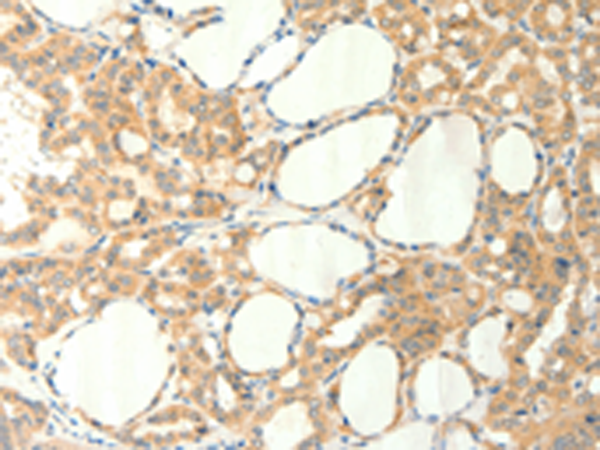

分类: 科研抗体货号: P04592别名: BIG2; PVNH2; dJ1164I10.1应用: IHC反应种属: Human, Mouse, Rat